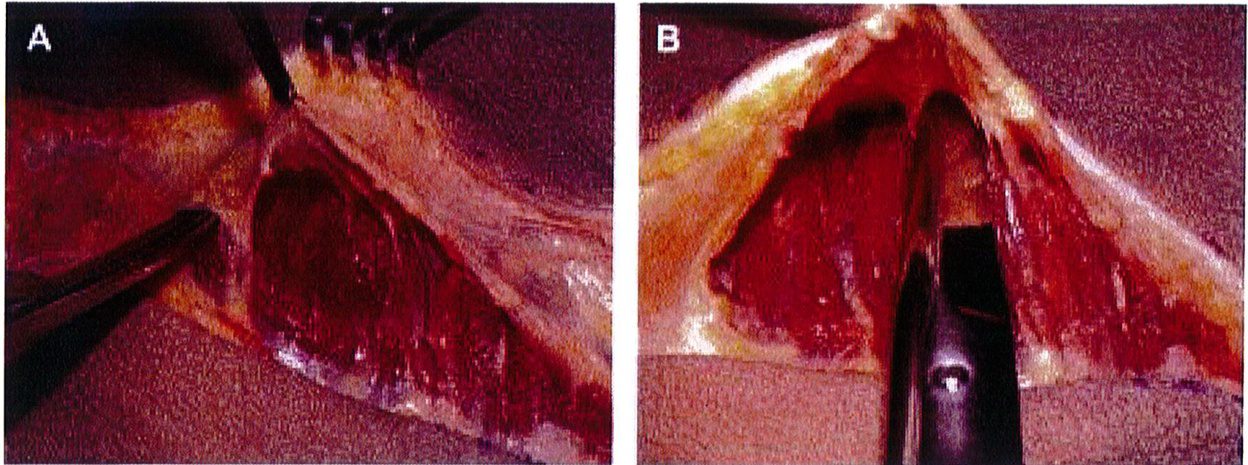

Hình. 3. (A) Lớp cân mạc che phủ cơ mông lớn. (B) Bóc tách lớp cân và cơ để tạo mặt phẳng cấy ghép. (Trích từ de la Pena JA, Rubio OV, Cano JP, et al. Subfascial Nâng mông. Clin Plast Surg 2006;33:409; đã xin phép trước khi đăng tải.)

Dụng cụ bóc tách hai đầu tù, hình tròn được sử dụng để phân tách mặt phẳng vô mạch đã được bộc lộ bằng cách tiêm dung dịch trước đó, nhằm bảo tồn tối đa vách và lớp cân mạc. Nên thực hiện bóc tách từ trong ra ngoài, từ trên xuống dưới với một dụng cụ banh có đèn sợi quang (Hình 10). Để tách các vách ngăn, sử dụng một cây bóc tách dài có một đầu nhọn hoặc kéo dài (Hình 11). Các nhánh động mạch mông trên, mông dưới và một số mạch nuôi cho vùng cân mạc được đốt điện. Hãy chắc chắn

khu vực dưới cân, từ đó có thế bóc tách được lớp cân mạc nguyên vẹn (Hình 9). Các vách ngăn này chạy cùng chiều với các bó cơ mông mà chúng che phủ tương ứng, nên khi bóc tách trông chúng như đang tỏả ra như hình rẻ quạt.

Hình. 9. Đánh dấu các mốc giải phẫu quan trọng. (A) Đường rạch cân cơ mông lớn bắt đầu từ bờ ngoài xương cùng (B) Bắt đầu bóc tách lớp cân từ đường rạch ban đầu (Trích từ de la Pena JA, Rubio OV, Cano JP, et al. Subfascial Gluteal aug- mentation. Clin Plast Surg 2006;33:411; đã xin phép trước khi đăng tải.)